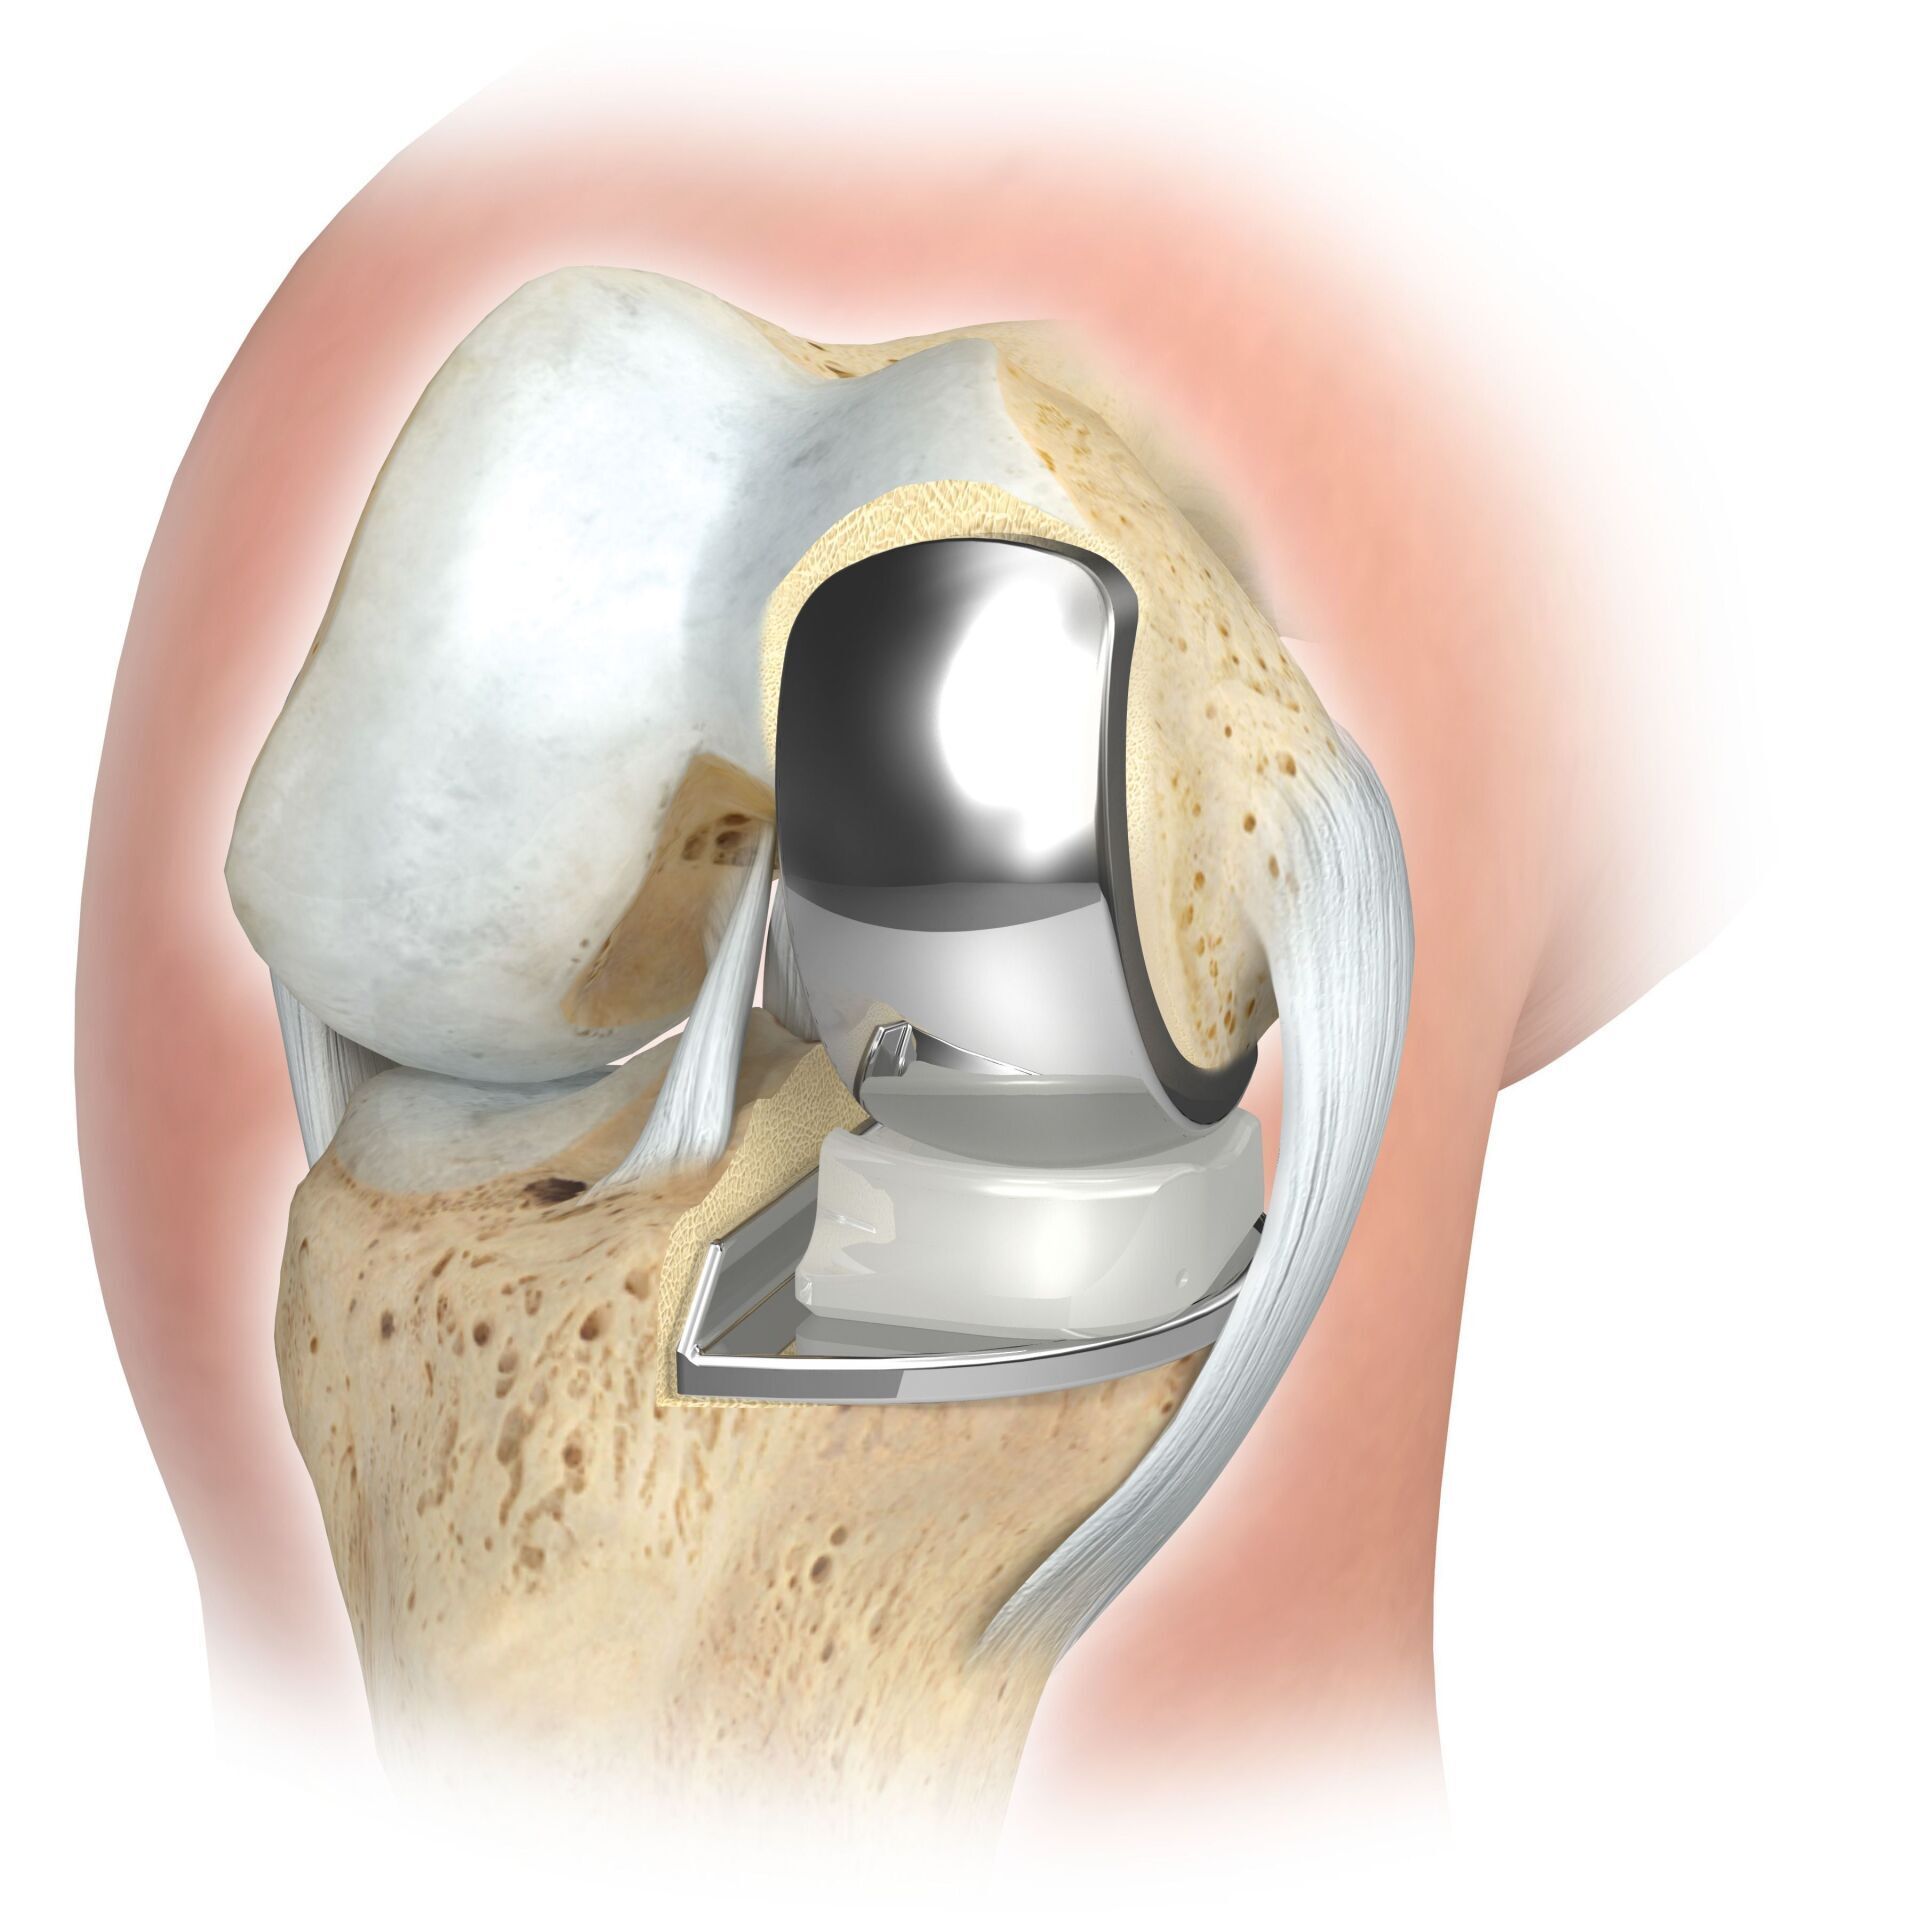

ATR (ARTICULACIÓN ARTIFICIAL DE LA RODILLA)

La articulación de rodilla artificial reemplaza la superficie del cartílago destruida por la osteoartritis. El hueso subyacente del fémur y la cabeza tibial permanece intacto. Algunos comparan una articulación artificial moderna de rodilla con la coronación de un diente; el término exacto es el llamado rejuvenecimiento bicondilar. Entre las nuevas superficies de la parte superior e inferior de la pierna se encuentra la llamada incrustación de un plástico blanco especialmente endurecido, que en la imagen de rayos X se puede ver como la distancia entre las piezas metálicas.